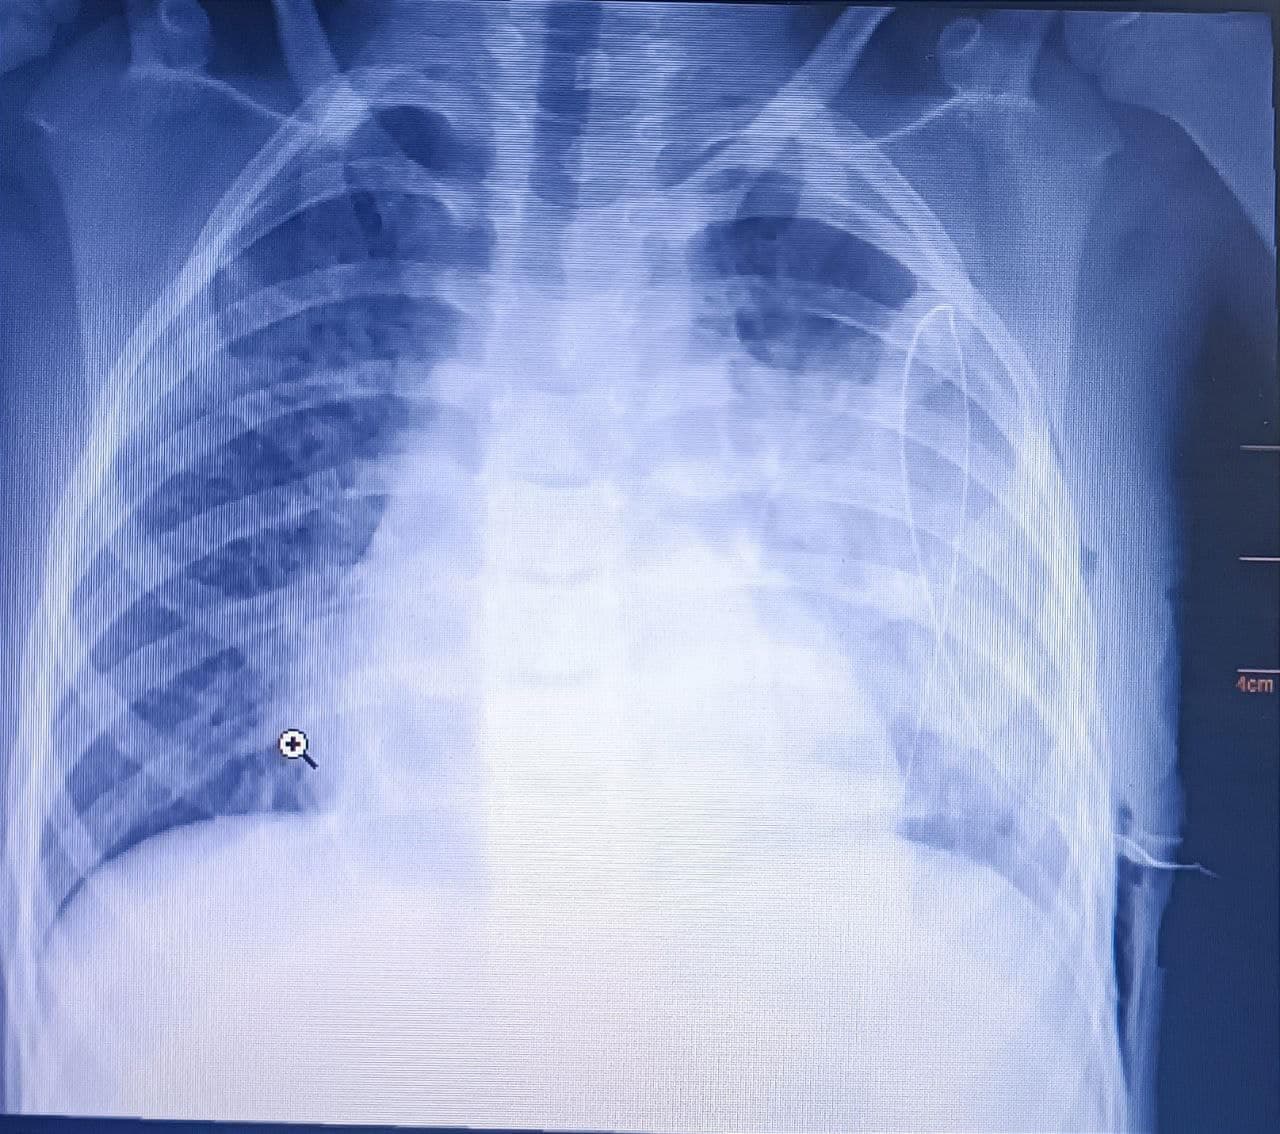

Першим симптомом хвороби була висока температура. Дитину лікували антибіотиками, однак легше не ставало. Згодом у 7-річного Матвія почали боліти плечі та груди, на рентгені виявили ознаки двобічної пневмонії та лівобічного ексудативного плевриту.

У Центрі дитячої медицини поставили діазгноз – двобічна, полісегментарна пневмонія, лівобічна деструктивна пневмонія, лівобічний ексудативний плеврит, лівобічний фібриноторакс. Тобто двобічне запалення легень, рідина в лівій плевральній порожнині та спайки, які створювали ефект бджолиних сот. Рідина була обмеженою і звичайним дренуванням її не можна видалити з плевральної порожнини.

Дитині провели торакоскопію, адгезіолізис. Це роз'єднання плевральних спайок. Також провели санацію та видалили з плевральної порожнини повітря, крові або рідини, розправили легені та ліквідували зміщення середостіння, яке спричиняє гемодинамічні порушення. Опісля ще продовжили медикаментозне лікування. Хлопчика вже виписали додому.